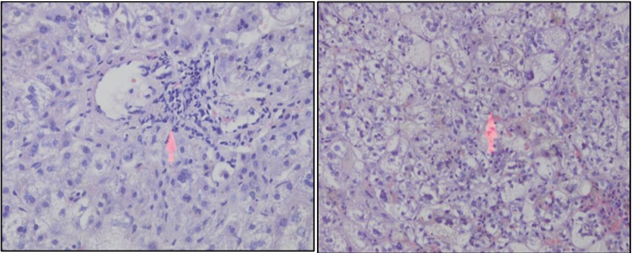

Abdominal ultrasonography

An abdominal ultrasonography examination should be obtained as part of the early evaluation of a cholestatic infant to assess liver structure, size, and composition; to evaluate for the presence of ascites; and to identify findings of an extrahepatic obstructive lesion (CC, mass, gallstone, and sludge).2 Abdominal ultrasonography findings described in BA include the triangular cord sign (cone-shaped fibrotic mass >4mm anterior to right branch of portal vein), abnormal gallbladder morphology (not visualized or length <1.9cm or lack of smooth/complete echogenic mucosal lining with an indistinct wall or irregular/lobular contour), poor contractility (<60%) of the gallbladder 2hours after oral feeding (Figure 15). A distended gall bladder, however, does not rule out a proximal BA with a distal patent bile duct and mucus filled gallbladder.2,4 It is recommended that ultrasound should be done after 4hours of fasting. Ultrasound can also detect polysplenia or asplenia, interrupted inferior vena cava, preduodenal portal vein, and situs inversus; all of these conditions would strongly suggest BA splenic malformation syndrome and other laterality defects. CBD dilation is not seen in BA and suggests a distal obstruction or a forme fruste CC. In normal infants CBD is seen with difficulty (<2mm diameter). Hence non-visualisation of CBD is not synonymous with BA. Cyst at porta may be seen in BA and can be differentiated from CC by the absence of intrahepatic biliary dilatation and rudimentary gall bladder (Figure 16). 2

Figure 15: The triangular cord sign in abdominal ultrasonography.

Figure 16: Abdominal ultrasonography findings in type-I choledochal cyst.